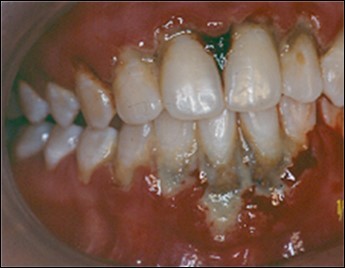

The patient under hard emotional stress that associated with bacterial plaque promoted ANUG with necrosis of alveolar bone and marginal gingival soft tissue in 31 and 41 (Figure 1). The patient was free of systemic disease and was not currently receiving any medication. Initial therapy was carried out using Er-YAG laser, to promote scaling and root planning and oral hygiene instruction. After initial therapy (Figure 2) the surgical method employed consists of the following steps as described by Langer and Langer5.

Figure 1.ANUG

ANUG